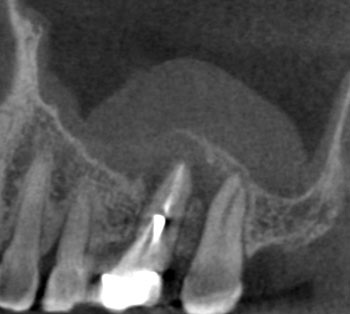

Case 3: A lateral lesion with a superficial crack

This patient presented for a second opinion after an endodontist recommended extraction for tooth #31 because of a VRF on its distal root. A deep isolated probing defect, a cervical sinus tract, the lateral position of the periradicular lesion and the prior placement of a full crown because of cracks in the tooth’s distal enamel marginal ridge likely contributed to the prior diagnosis of VRF.

A new diagnosis of previously treated and chronic apical abscess was made, but the possibility of a VRF was discussed with the patient. RCT was initiated. Internal examination of the pulp chamber reassuringly revealed that a crack on the distal wall of the pulp chamber did not extend to the pulpal floor. Treatment was completed in three visits using a calcium hydroxide intracanal medicament. Treatment and postoperative radiographs revealed a sharp dilaceration of the distal root, likely focusing the bony lesion toward the distal surface, not toward the root apex. Four months later, soft tissue and bony healing were confirmed.

Fig. 9: Preop PA.

Fig. 10: Preop CBCT.

Fig. 11: Preop probe.

Fig. 12: Recall PA.

Fig. 13: Recall CBCT.

Fig. 14: Recall probe.